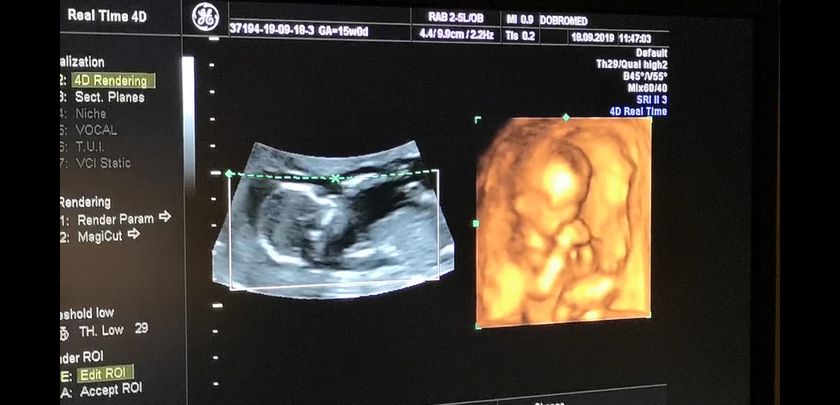

14 недель и 7 дней, нам врач сказала что точно видно мошонку и это мальчик… но я не уверена ? у него пуповина между ног была, короче я запуталась.

На 1 скрининге нам предположили что будет девочка, а тут сюрприз вырос....... Может всё таки пуповина? ?

Ну у вас только 15 недель, мне 100% сказали пол в 19 недель. На 2ом узи. Чуть подождите.

На 2-ом скрининге скажут точно